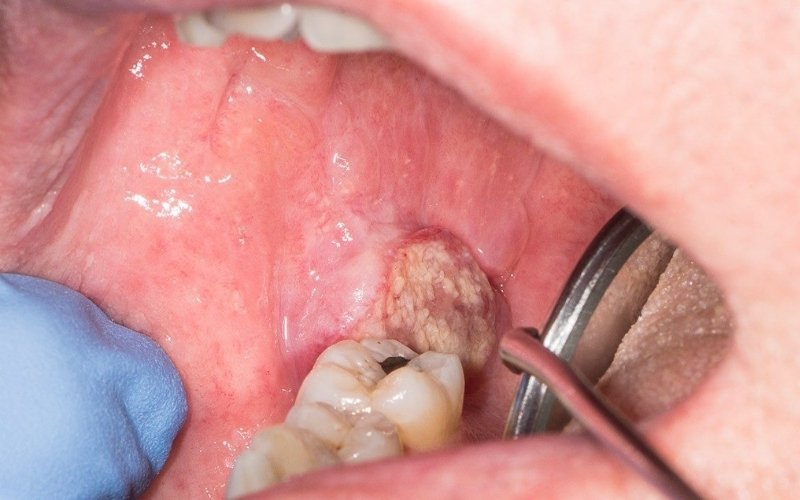

Dr. Bhavin Vadodariya is a highly trained surgical oncologist with extensive experience in treating cancers of the head, neck, thyroid, oral cavity, and more.

With expertise in minimally invasive techniques, microvascular reconstruction, and complex head-neck surgeries, Dr. Bhavin focuses on reducing pain, and improving long-term outcomes.

Dr. Bhavin Vadodariya treats a wide range of cancers including oral cancer, thyroid cancer, head & neck cancers and breast cancer with advanced surgical care.